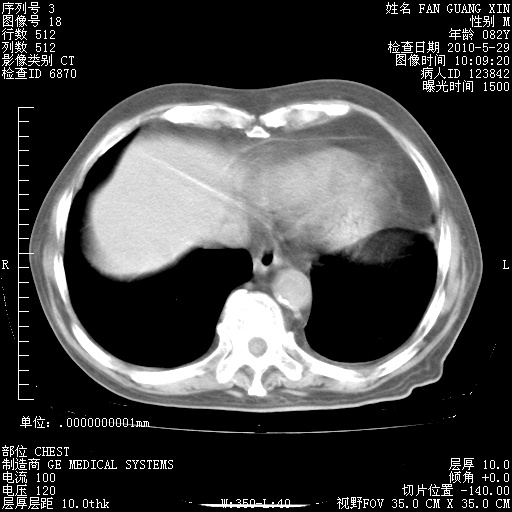

发表于 2010-5-19 19:23

还需要哪些辅助检查?我们医院排除真菌感染没有任何检验方法,胸片好像能够排除肺部真菌感染。

补充:ENA化验全部阴性。免疫五项(IgG、IgA、IgM、C3、C4)只有C4略高。